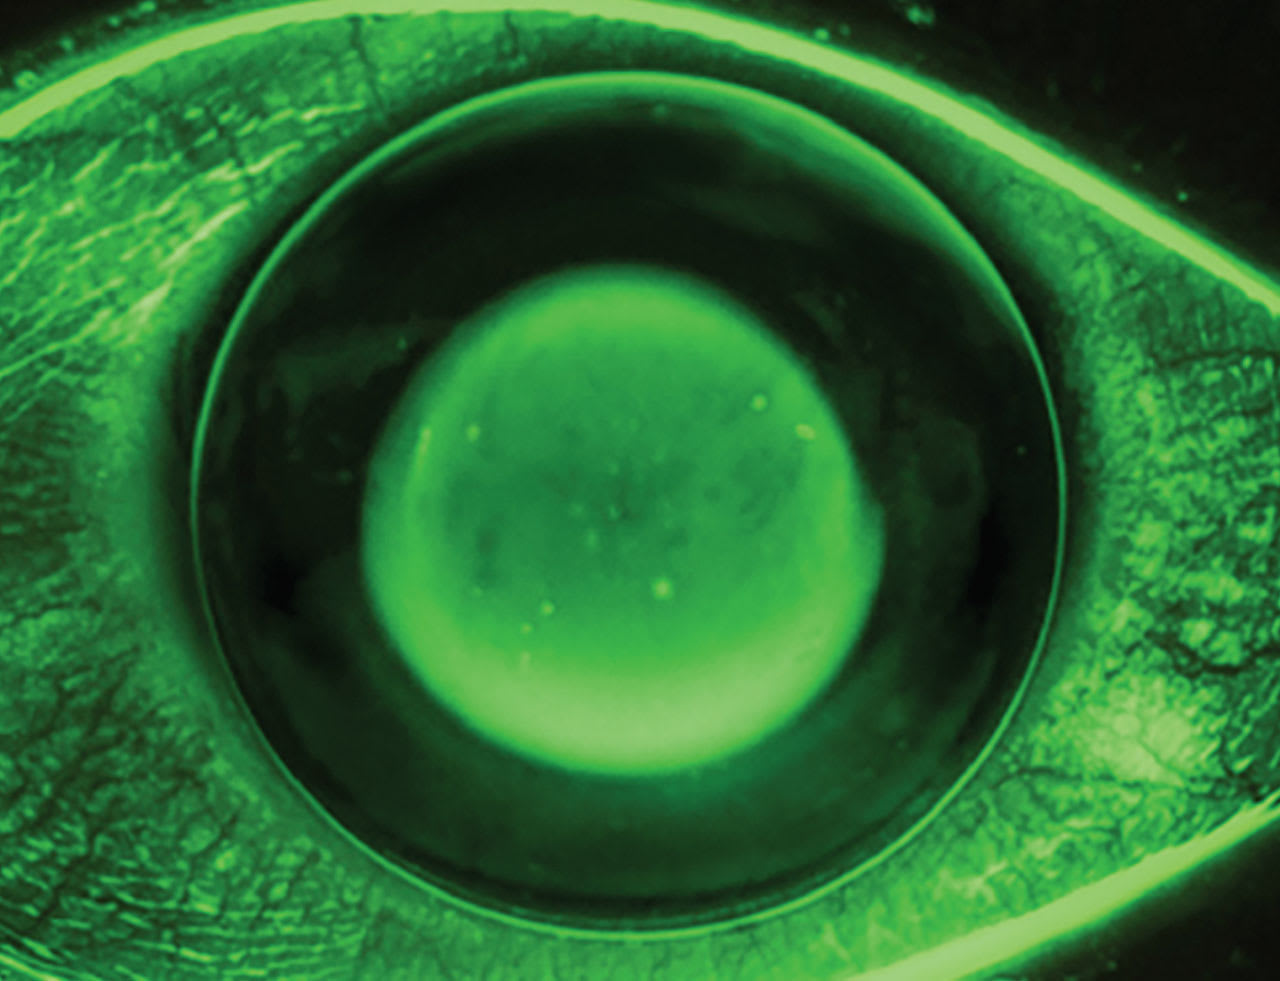

An ortho-k lens that is too shallow will resist exchanging the tear layer over the central cornea and cause central epithelial breakdown (Figure 2). A shallow lens may also show excessive edge lift, as the lens is bearing primarily on the central cornea. When edge lift is present, determine if the lens is too shallow or if the edges are too flat.

A lens that is too deep will show excess NaFl over the central cornea and is associated with a central island on topography. In this case, the patient will require more minus power in their manifest refraction than anticipated. Although it seems logical to flatten the base curve to correct the residual myopia, the correct remedy is to reduce sagittal depth to properly influence the epithelium. Deep lenses may also decrease tear exchange or show minimal edge lift (Figure 3).